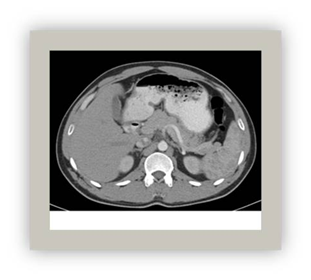

Computed tomography

This is an imaging technique that provides complete anatomical information of a region of the human body since it images the entire region. It offers images in axial plane which can be reformatted into other planes an even turned into three-dimensional images thanks to volumetric data acquisition (Figure 4).28,30

Figure 4 Contrasty abdominal CT horizontal section.